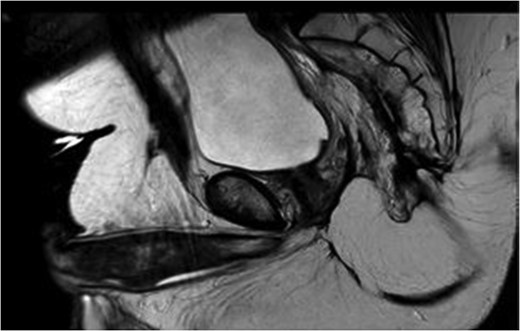

MRI pelvis. T2 axial image through pelvis demonstrating limited response to chemoradiotherapy with tumoral margins still predicted positive.